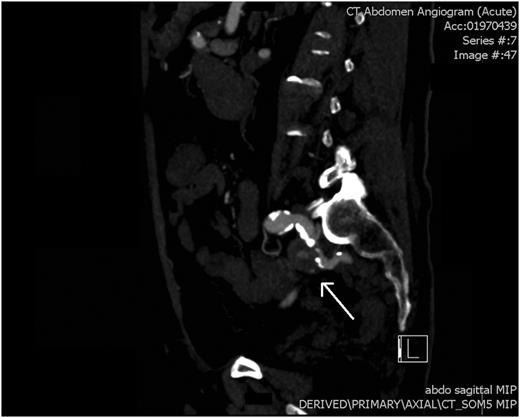

An arterial phase CT abdomen with IV contrast was performed. This revealed a contrast blush within the descending colon closely associated with an aneurysm of the internal iliac artery. The possibility of an arterial fistula to the colon was raised, and a vascular surgery consult was sought. Angiography confirmed a false aneurysm arising from the proximal aspect of the left internal iliac artery along its medial and inferior wall. Endovascular coil embolization was performed with occlusion of the vessel at the level of the aneurysm.

This patient had an isolated pseudoaneurysm of the internal iliac artery resulting in an arterio-colic fistula (Fig. 1). Isolated aneurysms of the internal iliac artery themselves are a rare phenomenon, estimated to account for only 0.3–0.4% of all intra-abdominal aneurysms. Forty per cent of patients with isolated internal iliac aneurysms will present with a rupture, with mortality estimated to exceed 50% in such patient groups [3].

CT angiogram: a saggital view showing pseudoaneurysm of the left internal iliac artery (white arrow).